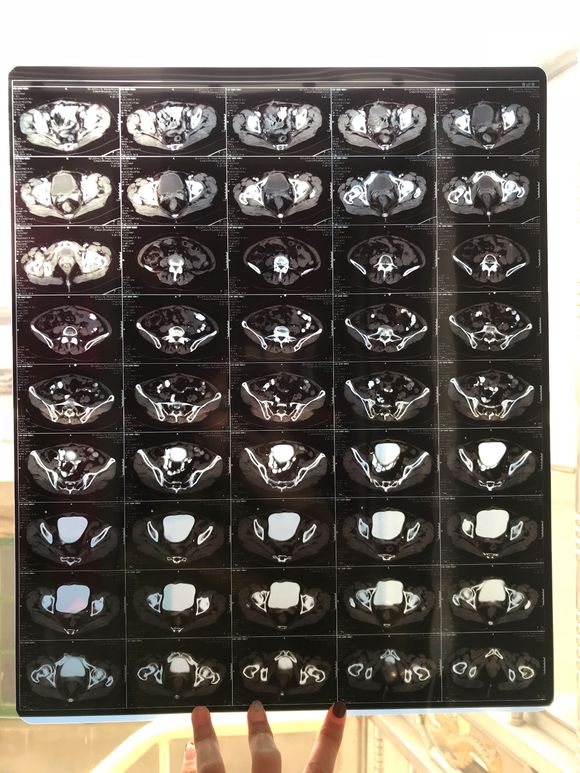

和你的故事 02019-04-09 患者家属我妈妈的病理结果报告,3期c1,大家可以帮忙看看吗,跪求了!我很急,谢谢!想知道是否严重,目前等术后出院后去肿瘤医院...

0人关注 4个回复 3625次浏览 -